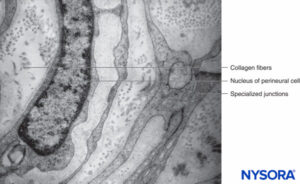

PERINEURIUM

Each fascicle is surrounded by a connective tissue sheath, the perineurium. The perineurium consists of concentric layers of flattened cells separated by layers of collagen (Figures 12 to 16). The number of perineurial cell layers depends on the size of the fascicle. As many as 8–16 concentric layers may be present around large nerve fascicles, but a single layer of perineurial cells surrounds small distal fascicles. In larger peripheral nerves, concentric cell layers alternate with layers of collagen fibers arranged longitudinally, similar to those of the epineurium. Collagen fibers are thinner than those of the epineurium, and only a few elastic fibers are scattered among them. Perineurial cells have a basal lamina on each side that may be considerably dense. At sites known as hemidesmosomes, the perineurial cell plasma membrane strongly adheres to the basal lamina.

FIGURE 12. Concentric perineurial layers. Transmission electron microscopy. Magnification ×30,000. (Reproduced with permission from Reina MA, Arriazu R, Collier CB, et al: Electron microscopy of human peripheral nerves of clinical relevance to the practice of nerve blocks. A structural and ultrastructural review based on original experimental and laboratory data. Rev Esp Anestesiol Reanim. 2013 Dec;60(10):552-562.)

FIGURE 13. Perineurial layers and specialized junctions. Transmission electron microscopy. Magnification ×20,000. (Reproduced with permission from Reina MA, Arriazu R, Collier CB, et al: Electron microscopy of human peripheral nerves of clinical relevance to the practice of nerve blocks. A structural and ultrastructural review based on original experimental and laboratory data. Rev Esp Anestesiol Reanim. 2013 Dec;60(10):552-562.)

FIGURE 14. Collagen fibers among perineurial layers. Transmission electron microscopy. Magnification ×30,000. (Reproduced with permission from Reina MA: Atlas of Functional Anatomy for Regional Anesthesia and Pain Medicine. New York: Springer; 2015.)

With electron microscopy, perineurial cells are seen as thin sheets of cytoplasm containing small amounts of endoplasmic reticulum, filaments, and numerous endocytic vesicles. Tight junctions and gap junctions between adjacent cells within the same layer of perineurium are also observed. Similar tight junctions may also appear between successive layers of the perineurium when their cells are in close proximity. Tight junctions in the inner layers of the perineurium and tight junctions in endoneurial capillaries form a blood-nerve barrier structure (Figures 17 and 18). The blood-nerve barrier is not equivalent to the blood-brain barrier as the blood-brain barrier astrocytes help regulate the flow of compounds between blood and the brain. The perineural cells are metabolically active, and their cytoplasms contain enzymes like ATPase (adenosine triphosphatase), 5-nucleotidase, and so on. These cells probably play a role in maintaining electrolyte and glucose balance around the nerve cells.